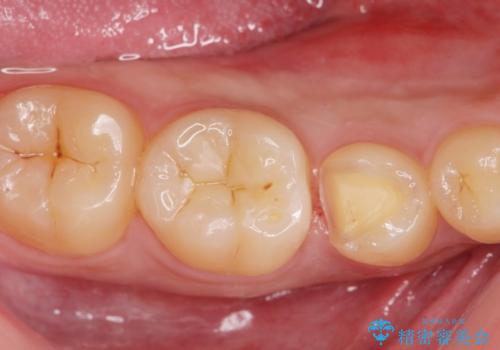

歯と歯の間に虫歯(コンタクトカリエス)がありましたので、拡大鏡下で虫歯を取り、白い詰め物(e-maxインレー)で治療を行いました。

適合の良い詰め物が入りました。